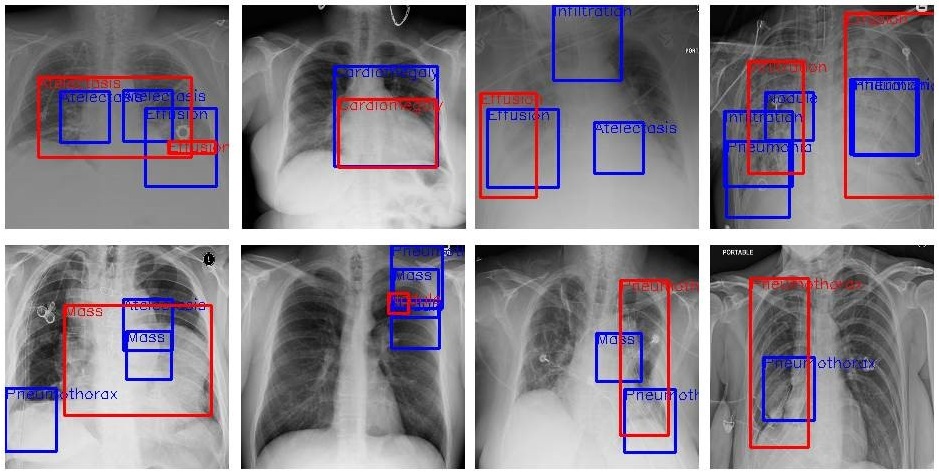

В передовой медицине, например, машинное обучение используют для выявления заболеваний. В программу загружается большое количество рентгеновских снимков с определенным диагнозом. Вместе со снимками в атрибутах базы данных присутствует описание болезни с характерной симптоматикой и изменениями показателей анализов. Алгоритм рассматривает каждое изображение в наборе данных и находит закономерности.

Модель машинного обучения учится распознавать болезнь. Чтобы протестировать алгоритм, разработчики создают 2 выборки — тестовую и тренировочную. Тренировочная выборка больше тестовой, поскольку именно на ней наша программа будет обучаться. После обучения мы тестируем точность алгоритма на данных для теста и смотрим результат.